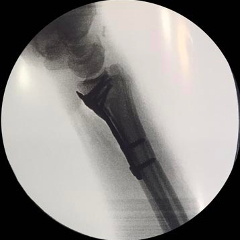

An incision is made in the forearm near the wrist. The broken bones are then exposed and aligned. Metal plates and screws are used to hold the bones in place. X-rays are then used to verify proper alignment and hardware placement.

Repair of Distal Radius Fracture With Plate and Screws